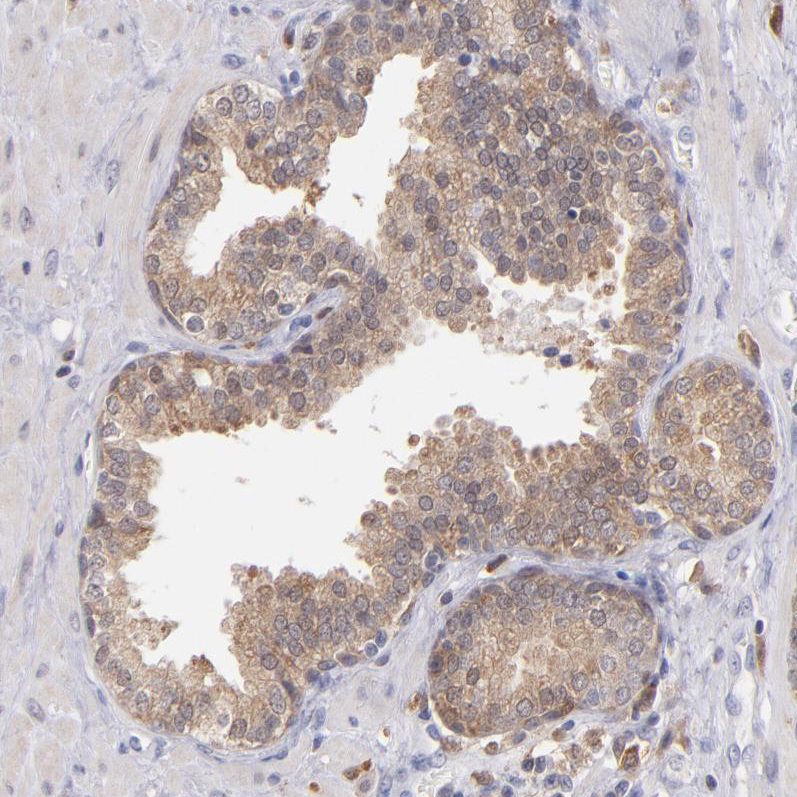

Immunohistochemistry analysis in human tonsil and skeletal muscle tissues using HPA001890 antibody. Corresponding PRKCD RNA-seq data are presented for the same tissues.